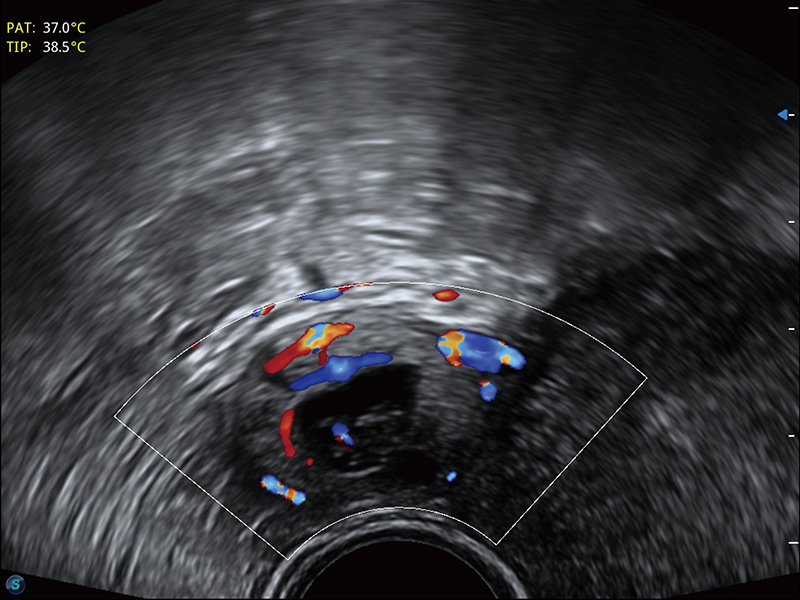

临床图

超声引导下胚胎移植

宫外孕血流